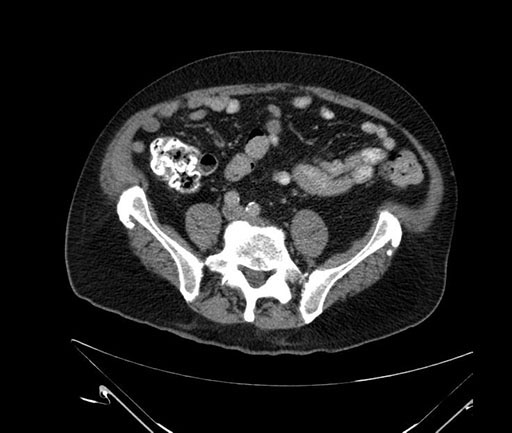

Whipple (pancreaticoduodenectomy) [case 7]

Imaging Analysis

Look through the patient's CT scan to identify any areas of concern for the necessary procedure.

Based on your CT findings, which issue(s) would give reason for "planned slowing down moment(s)" in this case?

Considering a standard Whipple procedure, what step(s) of the operation would you do differently in this case?